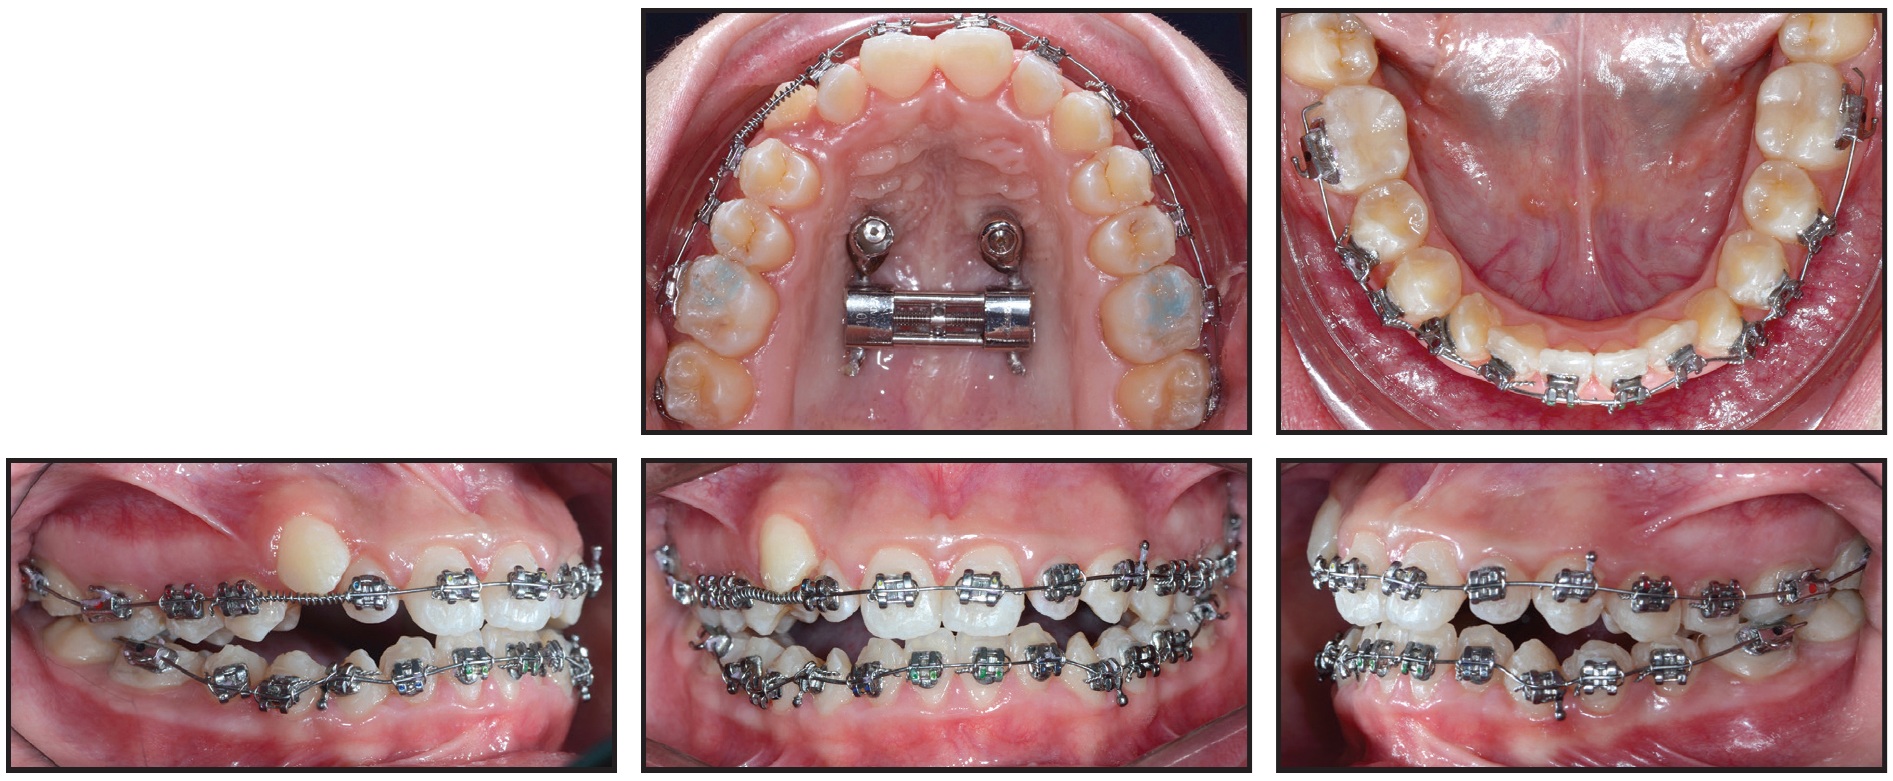

Primo** .022" labial brackets were bonded indirectly, and .014" nickel titanium archwires were inserted in both arches (Fig. 7). An open-coil spring was placed between the upper right lateral incisor and first premolar to provide space for eruption of the ectopic canine and to help center the upper dental midline.

Fig. 7 Primo** .022" labial brackets bonded and .014" nickel titanium archwires inserted in both arches; open-coil spring placed between upper right lateral incisor and first premolar to provide space for canine eruption and to center upper dental midline.

Two months later, when enough space had been created for the upper right canine, its eruption was initiated by tying an elastic module to its mesial bracket wings and to the archwire27 (Fig. 8).

After four months of canine alignment, an .019" × .025" nickel titanium archwire was inserted in the upper arch to continue leveling (Fig. 9). An .019" × .025" stainless steel archwire was inserted in the lower arch, with elastomeric chain added to close existing spaces and to prevent unwanted spaces from opening between the lower canines and lateral incisors. For sagittal and anterior vertical correction, the patient was asked to wear ³⁄16", 6oz Class III elastics*** 22 hours per day in a triangular configuration from hooks on the upper and lower canines to hooks on the upper first molars.

Fig. 8 Two months later, with sufficient space gained for upper right canine, eruption initiated with elastic module tied to mesial bracket wings and archwire.

Fig. 9 After four months of canine alignment, upper .019" × .025" nickel titanium and lower .019" × .025" stainless steel archwires inserted, with elastomeric chain added in lower arch for space closure.